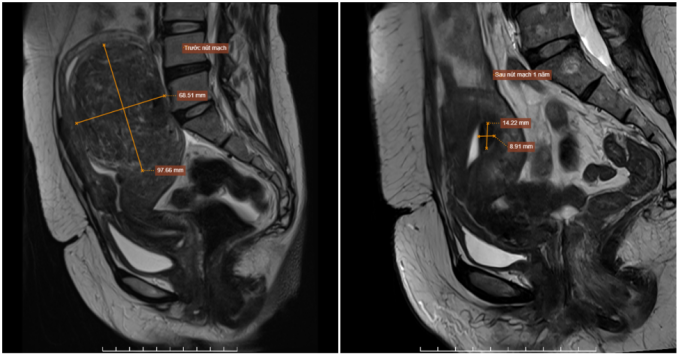

Hai năm trước, chị Lan phát hiện khối u xơ tử cung khoảng 4 cm nhưng không điều trị. Nay rối loạn kinh nguyệt kéo dài, chị đến Bệnh viện Đa khoa Tâm Anh Hà Nội chụp MRI cho thấy u xơ tăng lên tới 9,7x6,8 cm nằm trong lớp cơ tử cung, thành sau đáy tử cung, đẩy lồi niêm mạc tử cung. Bác sĩ chẩn đoán u có thể tăng sinh mạch mạnh, thuộc nhóm FIGO 2 - dễ gây rong kinh và đau bụng dữ dội khi hành kinh.